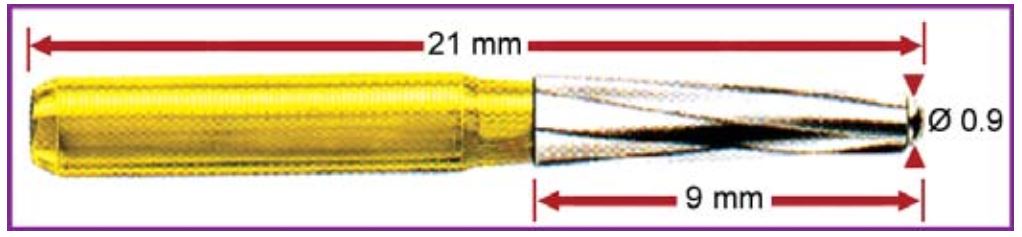

Các mũi khoan cần thiết cho mở tủy ngoài bộ dụng cụ cơ bản:

Để mở qua lớp men và ngà trên cùng thì cần các mũi khoan kim cương hoặc carbide (H5.2)